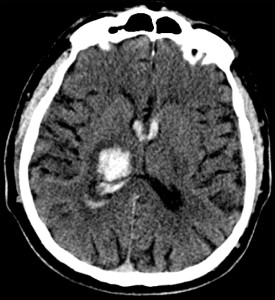

The study is a pooled analysis from the Oxford Vascular Study (OXVASC) and the Lothian Audit of the Treatment of Cerebral Haemorrhage (LATCH). It analyzed 674 first-time ICH patients over 1553 person-years. The cohort’s mean age was 74.7, 47% were male, and 51% were on antithrombotics before their ICH. Additionally, 22% had atrial fibrillation, and 47% had lobar ICH while the rest had non-lobar ICH.

The recurrent ICH rate was 3.2 per 100 person-years based on 46 events in the cohort. The ischemic stroke rate was 1.7 per 100 person-years from 25 events, and the rate for any serious vascular event was 7.9 per 100 person-years from 118 events. Lobar ICH had a higher risk of recurrent hemorrhage with a hazard ratio (HR) of 3.2 (95% CI 1.6-6.3; p=0.0010). Ischemic stroke risk was not location-dependent with an HR of 1.1 (95% CI 0.5-2.8; p=0.76). Atrial fibrillation at the time of the initial ICH increased ischemic stroke risk significantly (HR 8.2, 95% CI 3.3-20.3; p<0.0001).

The study accentuates the importance of two critical risk-stratification parameters for post-ICH management: the anatomical location of the hemorrhage and the presence of comorbid atrial fibrillation. The anatomical location, specifically whether it’s lobar or non-lobar, can be a predictive factor for the likelihood of recurrent hemorrhages. Conversely, atrial fibrillation is a crucial determinant for assessing the heightened risk of ischemic stroke. These risk stratification elements not only lend support to the findings of the RESTART trial but also underscore the urgency for specialized clinical trials that aim at targeted interventions for high-risk subgroups.

Check out some relevant images from our website below: